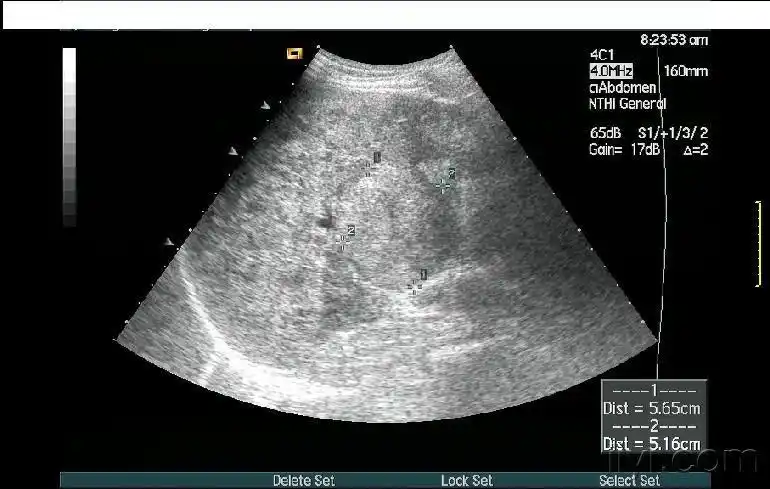

【超声】肝破裂超声,请战友欣赏

1.巨大肝破裂,贯穿尾状叶

超声入门贴157肝破裂